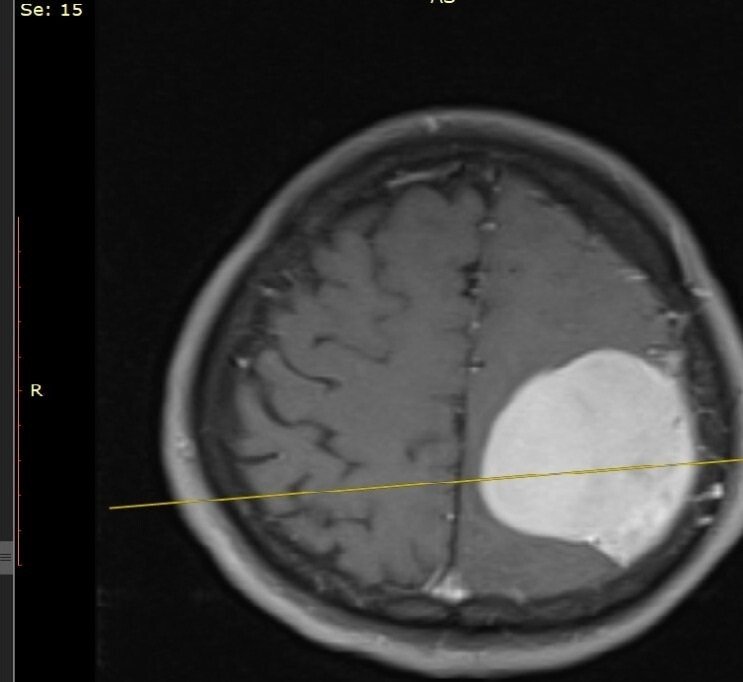

„Pacientul a fost internat ieri prin Unitatea de Primiri Urgențe, fiind diagnosticat cu o tumoră cerebrală gigantă care îi punea viața în pericol, prin comprimarea creierului. I s-au efectuat analize medicale, inclusiv testul pentru COVID-19. După studierea atentă a cazului am decis intervenția chirurgicală și am practicat rezecția completă a tumorii care a avut o mărime de 6/5 cm”, explică Șef Lucrări Dr. Vicențiu Săceleanu.

Intervenția chirurgicală, efectuată cu microscopul operator performant din dotarea secției, a durat aproximativ 4 ore. Operația a fost un succes și urmează ca pacientul să fie suspus unor controale post operatorii amănunțite.